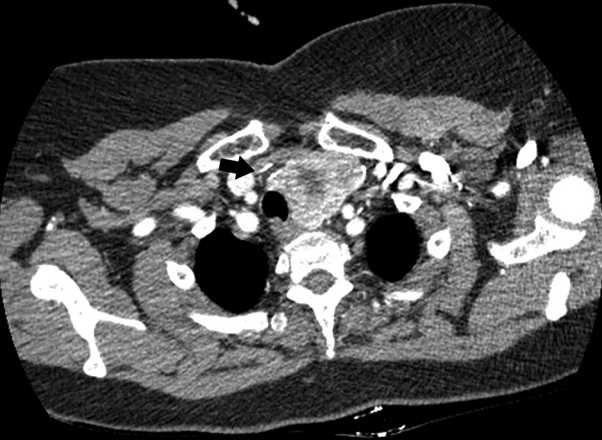

62세 여자 환자가 1년 전부터 좌측의 재발하는 압통과 크기 증가를 동반한 전경부 종물을 주소로 본원 내분비내과로 내원하였다. 1987년 우측 갑상선 일엽절제술 과거력이 있었으며, 갑상선기능검사상 thyroid stimulating hormone (TSH) 0.10 μIU/mL (0.27-5.0), Free T4 1.43 ng/dL (0.93-1.7), thyroglobulin-Ab <10 IU/mL (0-115), antimicrosomal-Ab 18.49 IU/mL (0-34)로 TSH 억제 소견이 확인되었다. 갑상선 초음파 검사에서 좌측 갑상선의 중간부에 30.8×28.7 mm의 크기로 경계가 분명한 혼합 에코성 결절이 보였으며 결절 내부로 미세석회화와 부분적인 저에코 병변을 포함한 결절이 관찰되었다(Fig. 1A and B). 결절의 우측으로 level VI 부위 20.7 mm 크기의 음향음영 및 다중반사를 동반한 혼합성 음영의 병변이 관찰되었다(Fig. 1C and D). 타병원에서 시행한 흉부 전산화단층촬영 검사상 불균질하게 조영 증강되는 좌측 갑상선 결절과 함께 결절의 우측으로 고음영 병변이 관찰되었다(Fig. 2). 경부 전산화단층촬영 검사와 세침흡인검사를 계획하였으나 환자의 거부로 시행하지 못하였고, 수술적 치료 원하여 이비인후과로 의뢰되었다.

Axial view of contrast enhanced chest CT scan showed that about 6.5×4.5×5.5 cm sized ill-defined enhanced left thyroid mass and about 1.7 cm sized hyperattenuated lesion in right level VI (arrow).